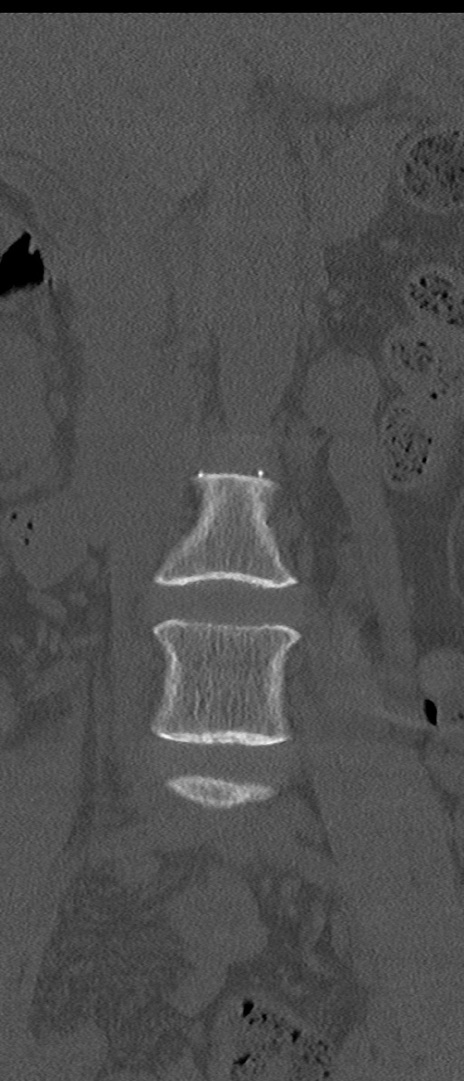

【整形】TIPS症例4 腰椎CT(冠状断像)

腰椎CT